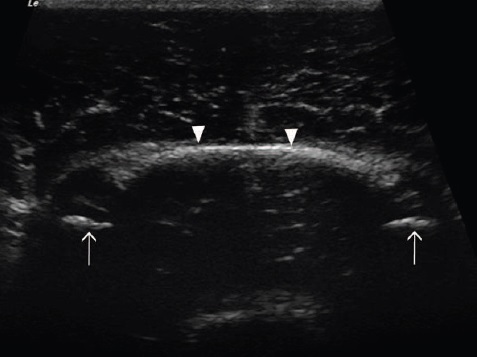

Fig 1: (a) Optimum position for the transducer. (b) Dorsal plane ultrasound image of the lateral aspect of a normal larynx.

Note the position of the cricoarytenoideus lateralis and vocalis muscle (small arrowheads) between the thyroid cartilage

(small arrows) and the arytenoid cartilage (large arrowhead). The cricoid cartilage (large arrow) is caudal to the thyroid

cartilage. Rostral is to the left of the image and caudal to the right